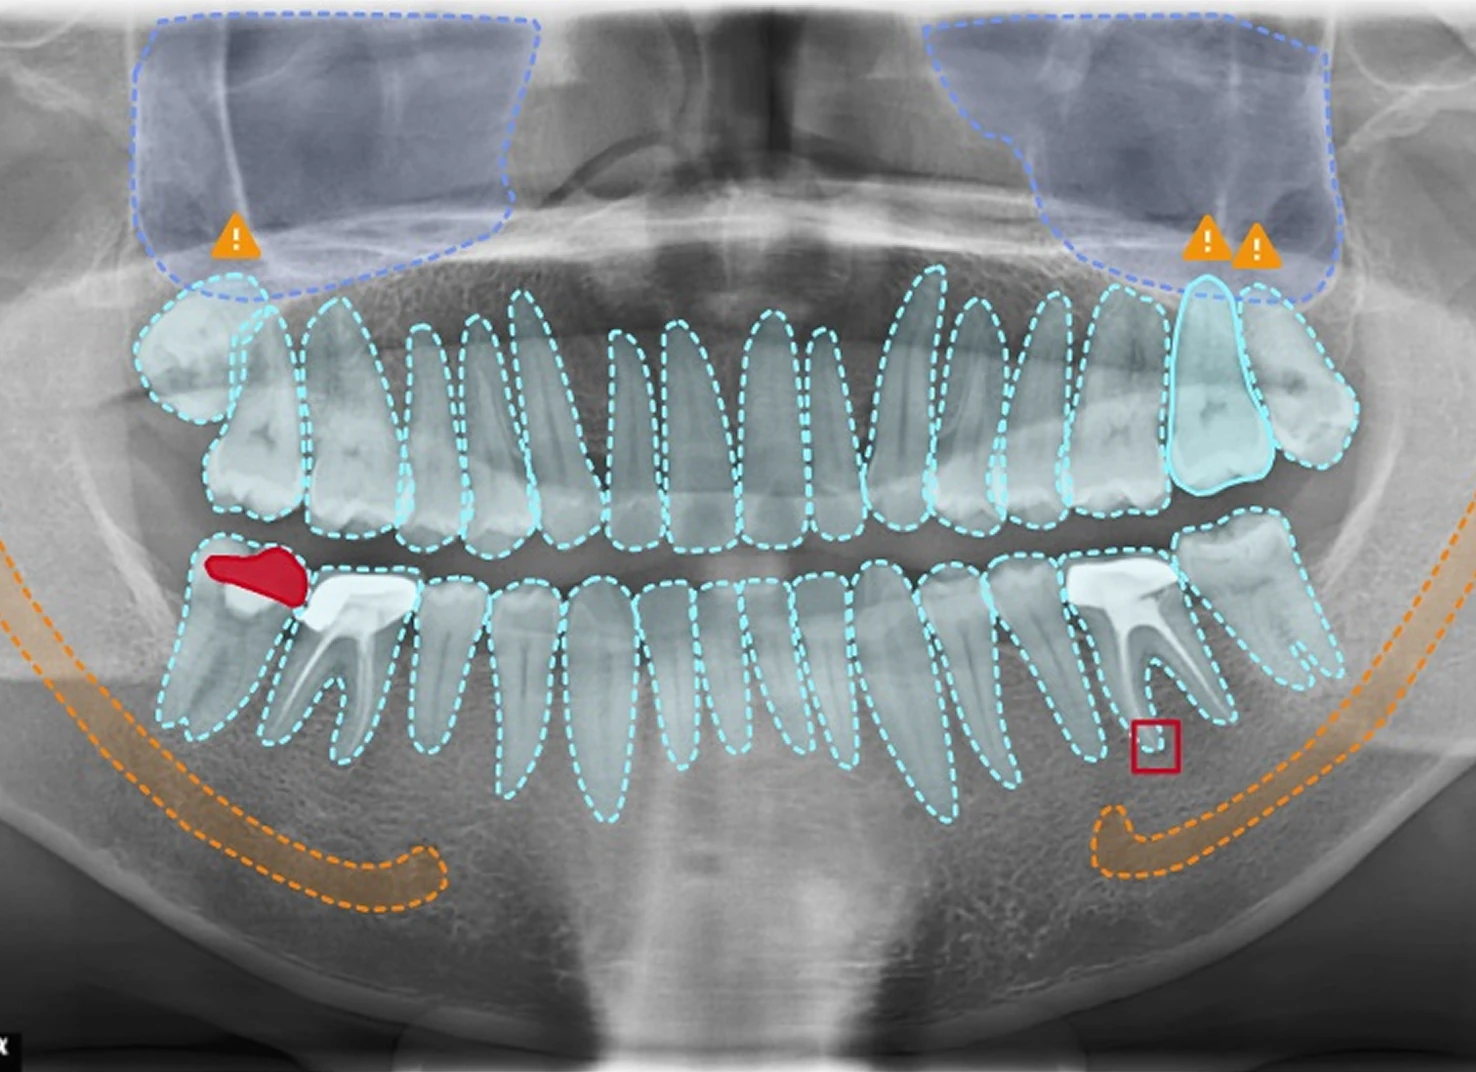

Ứng dụng AI phân tích hình ảnh nha khoa, hỗ trợ bác sĩ đưa ra quyết định lâm sàng nhanh chóng và tin cậy

Khám phá cách VICI Dentia hỗ trợ nha sĩ phân tích hình ảnh, phát hiện tổn thương sớm và nâng cao độ chính xác trong chẩn đoán lâm sàng.

Phát hiện tổn thương

- Tổn thương mất tổ chức răng

- Tổn thương cận chóp

- Bệnh/tình trạng nha chu

- Các tổn thương bệnh lý răng hàm mặt (u nang)

- Các chấn thương hàm mặt